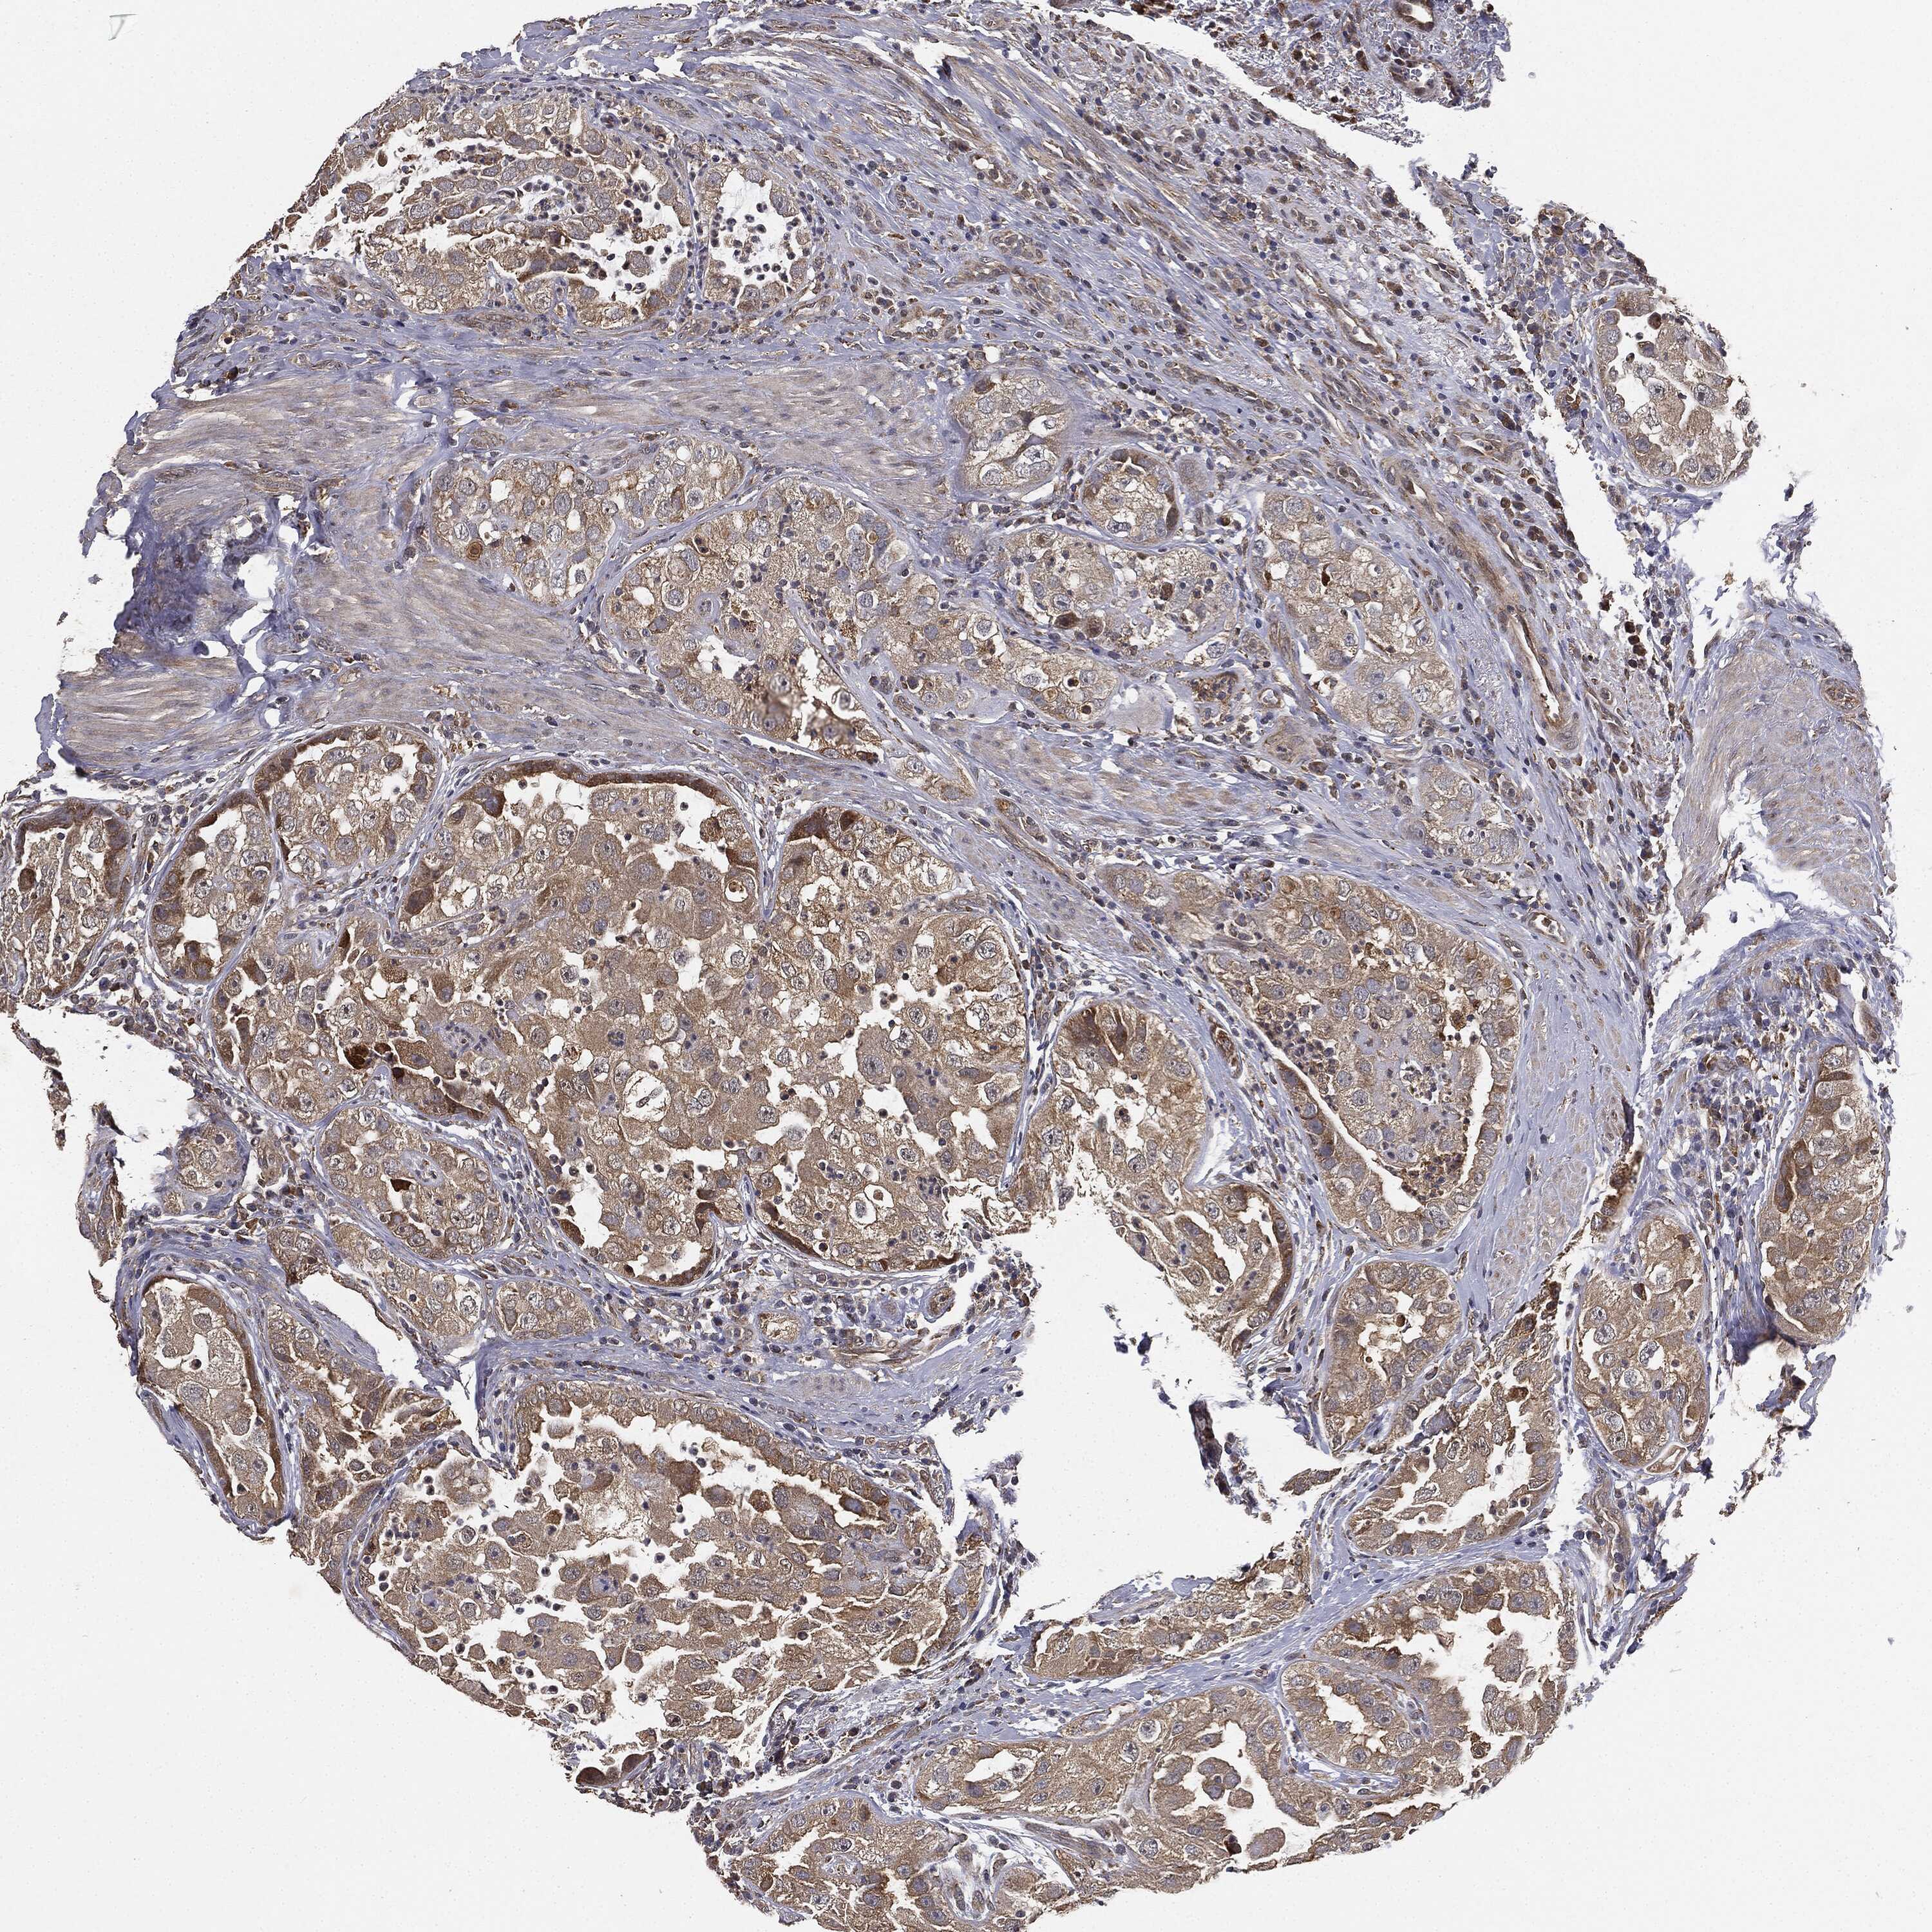

UROTHELIAL CANCER - Protein expressioni

A mouse-over function shows sample information and annotation data. Click on an image to view it in a full screen mode. Samples can be filtered based on level of antibody staining by selecting one or several of the following categories: high, medium, low and not detected. The assay and annotation is described here.

Antibody stainingi

Antibody staining in the annotated cell types in the current human tissue is reported as not detected, low, medium, or high, based on conventional immunohistochemistry profiling in selected tissues. This score is based on the combination of the staining intensity and fraction of stained cells.

Each image is clickable and will lead to virtual microscopy that enables deeper exploration of all samples and also displays staining intensity scores, fraction scores and subcellular localization as well as patient and tissue information for each sample.

Antibody HPA041439

Antibody HPA066153

Staining

High

Medium

Low

Not detected

Intensity

Strong

Moderate

Weak

Negative

Quantity

>75%

75%-25%

<25%

None

Location

Nuclear

Cytoplasmic/membranous

Cytoplasmic/membranous,nuclear

Urothelial carcinoma, High grade

Urothelial carcinoma, Low grade

Urothelial carcinoma, NOS